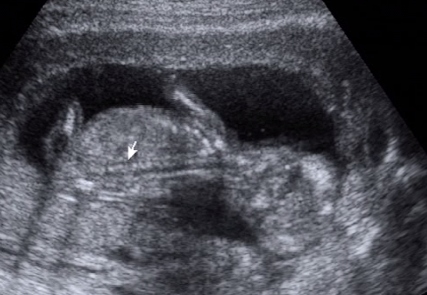

itt látszik a kuki

Kép [/u]

Pussz: Tigrisék